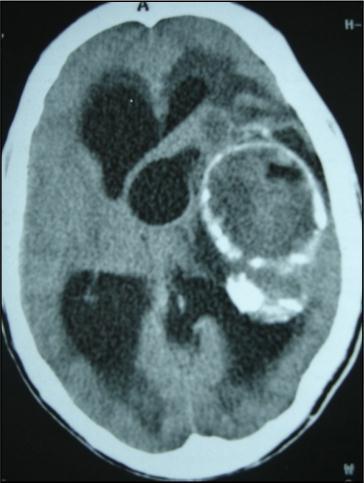

A 27 years-old male patient was admitted with 1 month history of headache, fever, short term memory lack, aphasia, right hemiparesis and seizures. He had liver hydatid cysts excised 8 years before and was treated with adjuvant medication (albendazole). The neurological examination revealed right central third cranial nerve palsy and hemi paresis, with Babinski sign positive, aphasia and papilledema on ocular fundus. The Glasgow Coma Scale was evaluated to 10/15 (E:3; V:1; M:6). A brain CT scan showed a large left temporoparietal intracerebral multiple and calcified hydatid cysts, important mass effect with midline shift about 7 mm following by an obstructive hydrocephalus (Figure 1). Other cysts were found in thalamic region (Figure 2). The Thoraco-abdominal CT scan showed multiple intra peritoneal hydatid cysts (Figure 3). A left temporo parietal craniotomy was performed in emergency. After corticectomy, using Arana-Iniguez technique, the appearance of the capsule suggested infected hydatid cysts with a purulent material which was aspirated. Numerous hydatid cysts were lifted away and several daughter vesicles were carefully removed without rupture (Figure 4). Macroscopically, the abscess wall appeared to be thick, calcified and tightly attached to lateral ventricular, so it could not be removed. The deep cyst overlying the third ventricle was left.in place. Microscopic examination demonstrated live scoleces, protoscoleces and multiple hooks. These findings are consistent with hydatid cyst (granulosis ecchinococcus) (Figure 5). Bacteriology examination found several white blood cells in the pus (neutrophilia) and infection by streptococcus pneumonia. This was consistent with infection. After surgery, the patient had medication (albendazole, specific antibiotherapy and phenobarbital). The inflammation assessment in the blood showed leukocytosis, a high C-reactive protein rate and increased erythrocyte sedimentation rate. Post operative CT scan was performed and showed the residual calcified capsule and decreased ventricular size (Figure 6). Clinical improvement was achieved after treatment. One month after the initial diagnosis, CT scan of the brain showed no recurrence and a physical examination revealed a neurologically intact, fully functional patient and eyes fundus normal. He was discharged and went to abdominal surgery two months later with complete intra abdominal cysts removal. Albendazole treatment was continuing for six months and radiological exploration was performed by brain MRI with spectroscopy at three and six month later. This showed that infection had resolved and the deep cyst overlying the third ventricle is less spherical (Figure 7, Figure 8). Four years later, the outcome was good.

Figure 2.axial CT showing another cyst located in thalamic region

Figure 3.Abdominal CT scan showing intraperitoneal hydatid cysts